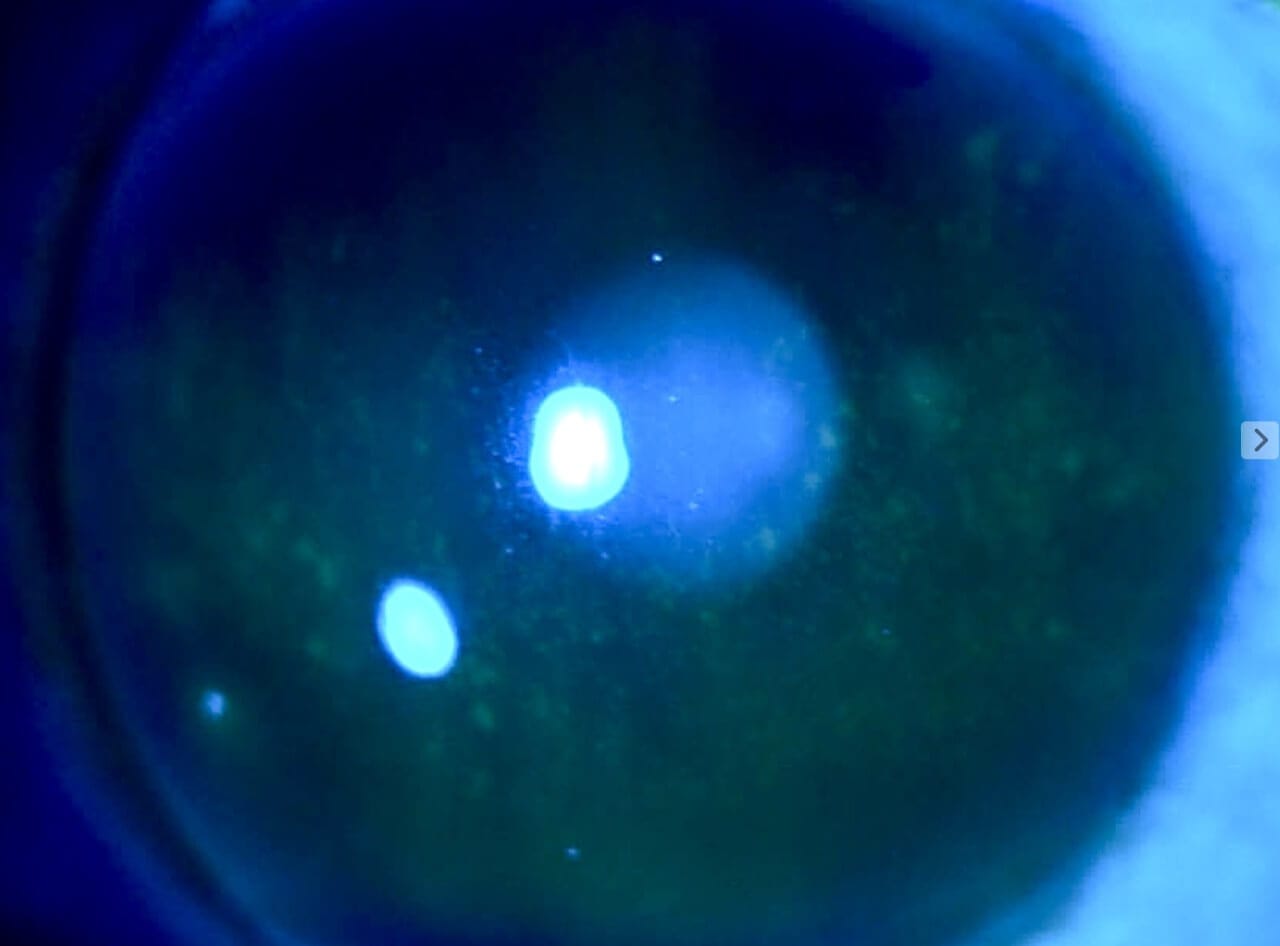

A 44-year-old female established patient was referred to the specialty anterior segment clinic for an evaluation due to unusual symptoms. She described a feeling of “a cold suction cup” on her right eye. The pertinent ocular history of the patient included decreased vision in her left eye due to optic atrophy from a childhood cystic lesion compressing the left optic nerve. There was no other pertinent medical or ocular history. Her surgical history included dental surgery, specifically a right upper impacted wisdom tooth extraction performed five years prior. The patient reported that a nerve was affected during the procedure and that she experienced severe pain on the right side of her face soon after the procedure. The intense pain continued for five years and was unsuccessfully treated with oral medications. The patient underwent a right-sided open skull base craniotomy for microvascular decompression of the trigeminal nerve to treat the trigeminal neuralgia. The patient reported experiencing right-sided facial numbness, intermittent blurry vision, and an uncomfortable right eye, with the inability to tear in the right eye soon after the procedure. Upon ocular examination, best-corrected visual acuity was 20/40 in the right eye, while the left eye showed no light perception. The left eye vision was stable, but her right eye vision had been 20/20 in prior eye exams. The right pupil was round and reactive to light, and a 4+ afferent pupillary defect was detected in the left eye, which was attributed to the left optic atrophy which was present since childhood. Confrontation visual field testing found a full-to-finger-count vision in the right eye, and the patient could not perform the test with her left eye. The sensitivity of the trigeminal nerve was assessed using a wispy cotton tip applied to the patient’s face and cornea. The patient was able to feel the cotton wisp on the left side of her face and cornea. However, she reported no sensation when the wisp was moved to the right side of her face (forehead, cheek) and cornea. She had some sensation on the lower right jaw. Slit lamp findings showed an intrapalpebral oval band of significant epithelial keratitis in the right eye, which stained with fluorescein but not with Rose Bengal. The stroma was intact and unremarkable. There was no keratitis noted in the left eye. A Schirmer’s test yielded results of 5 mm for the right eye and greater than 15 mm for the left eye. An InflammaDry test, which evaluates MMP9 levels in the tear film, was performed, yielding positive results in both eyes. Additionally, the proparacaine challenge test was performed, which did not improve her symptoms of a “suction cup” sensation. Intraocular pressures were within normal limits. A dilated fundus examination was unremarkable in the right eye and revealed a longstanding pale left optic nerve. A stage 2 neurotrophic keratitis was diagnosed in her right eye with a component of neuropathic pain. Multiple treatment options were discussed, including the placement of an amniotic membrane in the right eye. However, the patient was hesitant to proceed with this option since it was her only seeing eye. Cenegermin-bkbj 0.002% was prescribed to be used six times a day for eight weeks to address the neurotrophic keratitis in the right eye. Regular use of preservative-free artificial tears, spaced out at least 15 minutes with the cenegermin, was advised.

Figure 2. Corneal findings 6 months after treatment for eight weeks with cenegermin-bkbj and subsequent autologous serum.